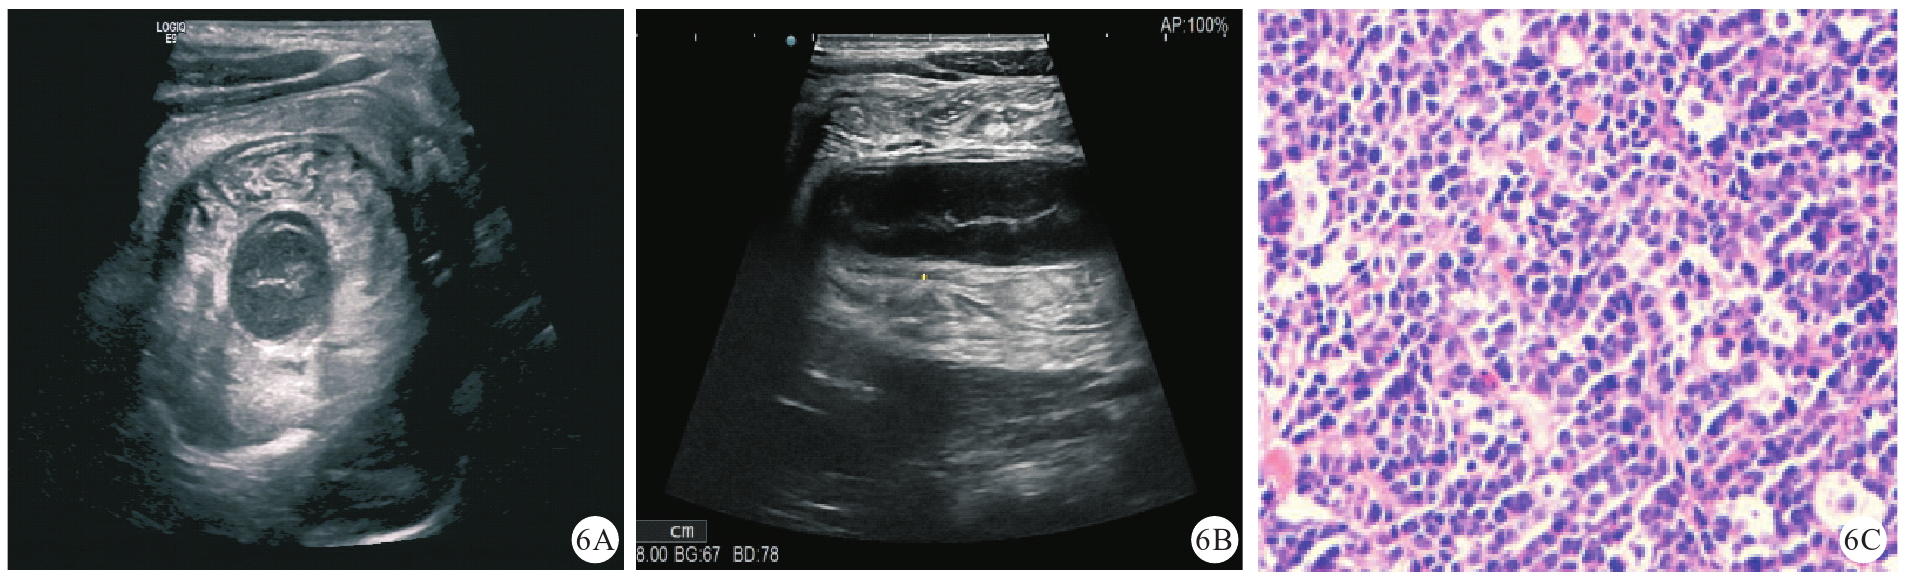

图6 本研究1例肠淋巴瘤继发性肠套叠患儿(男性,11岁1个月)的超声声像图及病理学检查图像[图6A:超声可见肠淋巴瘤继发肠套叠横断面套筒中心极低回声肠壁,未见系膜组织,套筒肠壁增厚,层次不清;图6B:超声可见纵断面套入部病变肠管增厚,呈极低回声;图6C:病理学检查结果提示肿瘤细胞弥漫分布,肿瘤细胞中等大小,细胞质稀少,可见核分裂象,提示Burkitt淋巴瘤(HE染色,高倍)]注:HE为苏木精-伊红